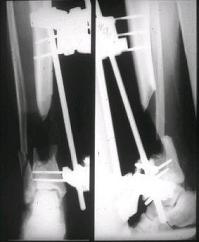

Tibialis anterior и M extensor digitorum L. Одновременно компактотомия костей голени в В/3 для замешение дефекта костей. #7;#8. Постепенно

исправлена ось и возмещен дефект. В результате восстановление тыльной флекcии стопы и функции конечности. #9;#10;#11